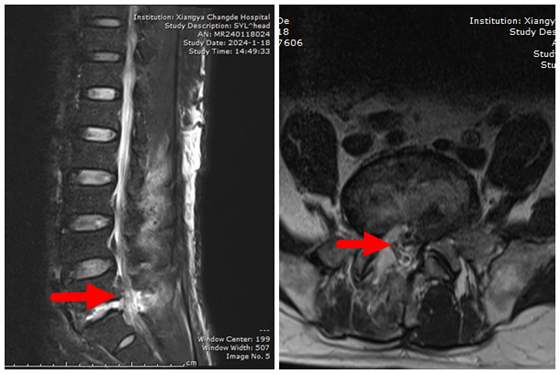

术后磁共振提示L5/S1突出椎间盘已摘除,椎管狭窄改善